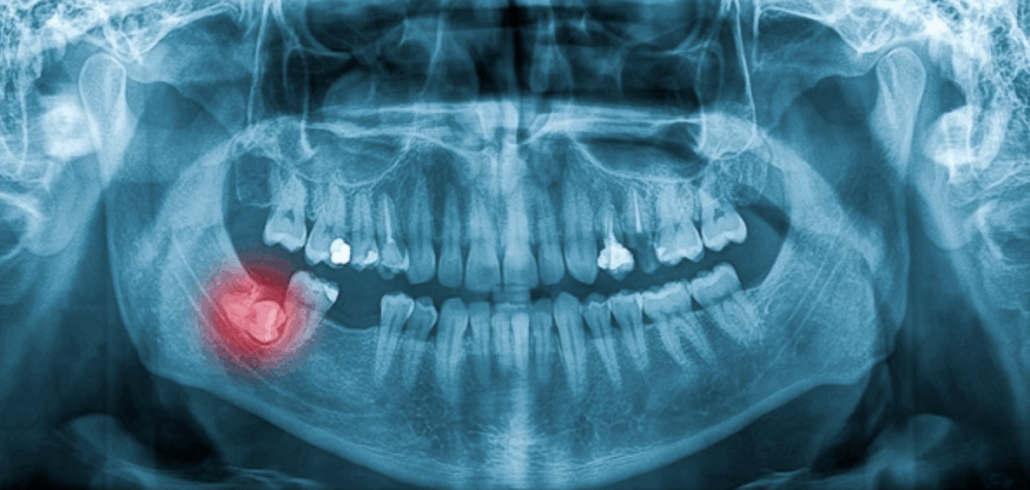

2. Examens préalables

-

radiographie panoramique

scanner 3D si la dent est proche du nerf ou du sinus

Ces examens permettent d’évaluer la position et le risque.